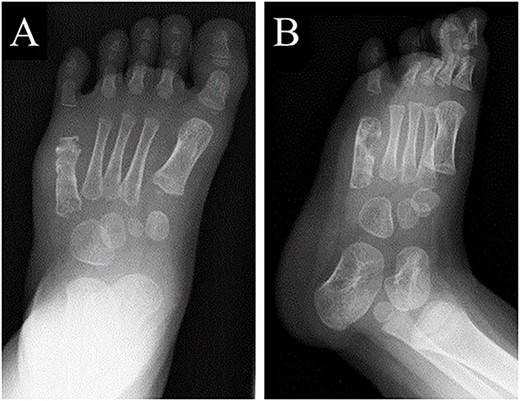

A 21-month-old Japanese female infant presented with a swollen mass on the dorsolateral aspect of the left foot. Her parents noticed the mass and brought the patient to our hospital. The patient had no past medical histories or complications prior to the occurrence. In addition, she received the BCG vaccine at the age of 4 months in Japan. At first visit to our hospital, physical examination revealed the ~3 × 3 cm mass was located on the dorsolateral aspect of the left foot and was hard accompanied by local heat (Fig. 1). Plain radiographs of the left foot showed a lytic lesion without periosteal reaction in the fifth metatarsal bone (Fig. 2). Magnetic resonance imaging (MRI) showed an isointense lesion on T1-weighted images and a hyperintense lesion on T2-weighted images around and within fifth metatarsal (Fig. 3). Gallium scintigraphy revealed intense uptake in the patient’s left foot (Fig. 4). In addition, laboratory examination was within normal. Based on medical history, clinical and imaging findings, we considered the possibility of neoplasia or osteomyelitis and performed an open debridement and biopsy of the lesion to make a diagnosis. The lesion was yellow and consisted of weak, adipose-like tissue that surrounded and continued into the inferior of the fifth metatarsal bone (Fig. 5). The lesion inside and outside the bone was resected as much as possible. Histopathologic examination of the lesion showed granulomatous inflammation including anaplastic giant cells, Langerhans-type giant cells and caseous necrosis (Fig. 6). Based on these results, TB or BCG osteomyelitis was considered as a diagnosis. The tuberculin test was positive, but the QuantiFERON TB test was negative. In addition, samples analyzed using polymerase chain reaction did not identify M. tuberculosis, but did identify the BCG Tokyo-172 strain. Per these findings, the patient was diagnosed with BCG osteomyelitis of the fifth metatarsal and oral treatment with anti-TB medicine including isoniazid (100 mg/day) and rifampicin (150 mg/day) was started. Clinical findings included reduction in swelling of the mass and gradual remodeling of the lytic lesion of the fifth metatarsal on plain radiographs (Fig. 7). However, 10 months after starting the anti-TB treatment, the mass recurred, and MRI revealed a residual high-intensity lesion around and inside the fifth metatarsal on T2-weighted fat-suppressed images (Fig. 8). It was determined that the lesion was difficult to control with anti-TB treatment alone, so an open debridement for the lesion was performed again. Histopathologic examination of the lesion revealed an epithelioid granuloma with necrosis. Therefore, the anti-TB treatment was continued. Six months after the second surgery, clinical and radiographic image findings showed complete improvement (Fig. 9). As a result, anti-TB treatment was ended. At the time of writing this report, 8 years after starting anti-TB treatment, there has been no recurrence.

Plain radiographs of the left foot showed the lytic lesion of the fifth metatarsal was remodeled gradually in (A) anteroposterior and (B) oblique views.